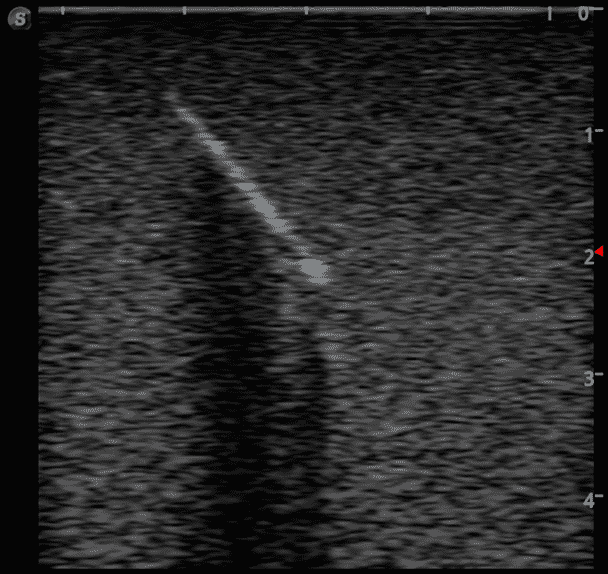

This training block is designed for training users in the techniques associated with ultrasound guided foreign body identification, targeting, and retrieval.

· High-quality ultrasound images

· Objects found in the human body including:

Glass shards

Wood splinter

Bullet

Plastic fragments

Metal fragments